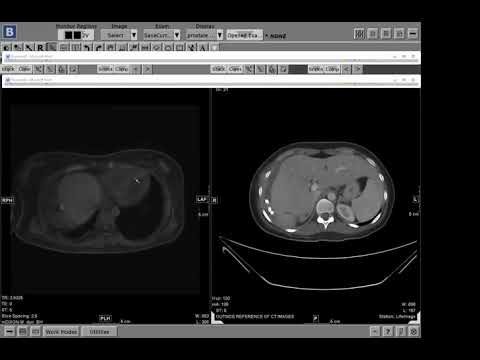

A companion hemangioma in an unusual spot (Victoria Chernyak)

Amyand's hernia (Victoria Chernyak)

Best way to diagnosis biilary leak? Dr. Victoria Chernyak

LI-RADS 2018 Update (Victoria Chernyak)

Aorto-caval fistula from rupturing AAA - Dr. Victoria Chernyak

How do you say "Bouveret"?? (Victoria Chernyak)

Intentional pneumoperitoneum - why??? (Victoria Chernyak)

Fast growing right renal mass w/ renal vein invasion (Dx Metastatic anal SCC | Victoria Chernyak)

Unusual gallbladder mass - Dr. Victoria Chernyak

Targetoid enhancement pattern pitfall - Victoria Chernyak | HCC